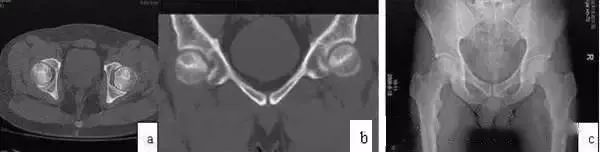

MRI出现阳性改变到CT扫描清楚显示病灶的间隔多数患者为6月~1年。CT可清楚显示Ⅱ期ONFH病灶,典型的改变为硬化带包绕坏死灶,部分ONFH的坏死灶内显示斑点状或片状骨化(图2)。Ⅲ期ONFH的CT扫描可显示股骨头病灶皮质骨断裂(冠状位、矢状位、或轴位重建)。因此,CT扫描对清楚显示病灶范围、部位、修复情况及鉴别Ⅱ、Ⅲ期有重要作用。

X线片的阳性改变较CT扫描还要延迟,多数病例X线片出现阳性改变在MRI确诊后的1年,少数患者可晚到2~3年,而且X线片的病灶显示均不清楚。因此,普通X线片对Ⅰ、Ⅱ期ONFH的诊断价值有限。但蛙式位X线片对显示新月征有其特殊价值。

图2 CT显示坏死灶明显,硬化带形成(a,b);X线片坏死灶显示不清(c)